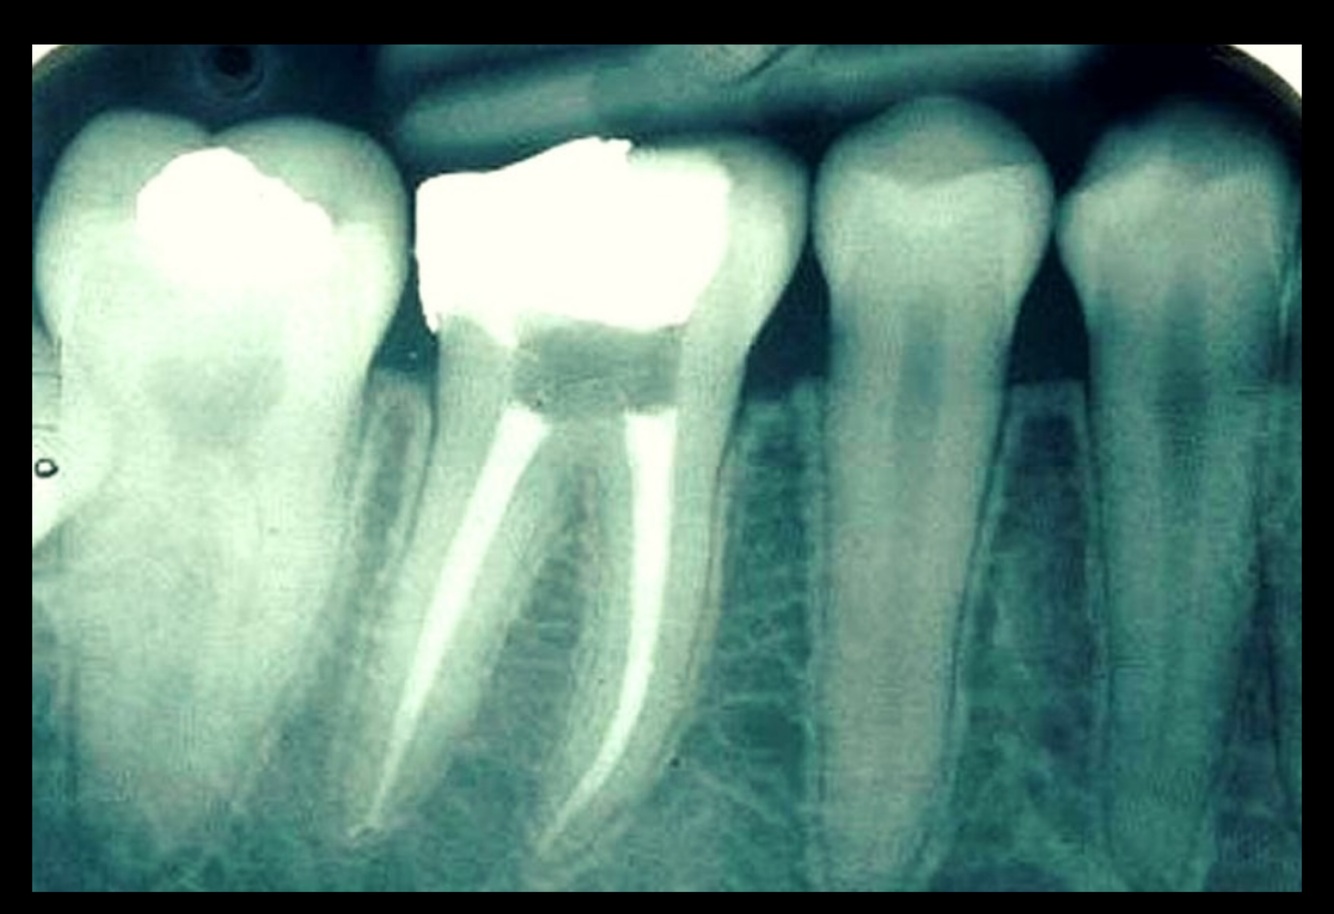

16

Q

Identify the restored tooth using both the long-hand and FDI notation systems

A

Upper right first molar,16

18

Identify the restored tooth using both the long-hand and FDI notation systems:

19

Which tooth was mistakenly recommended for extraction?

Referral “Dear Oral Surgeon, Please extract the unrestorable remaining roots: 17, 14, 26,”